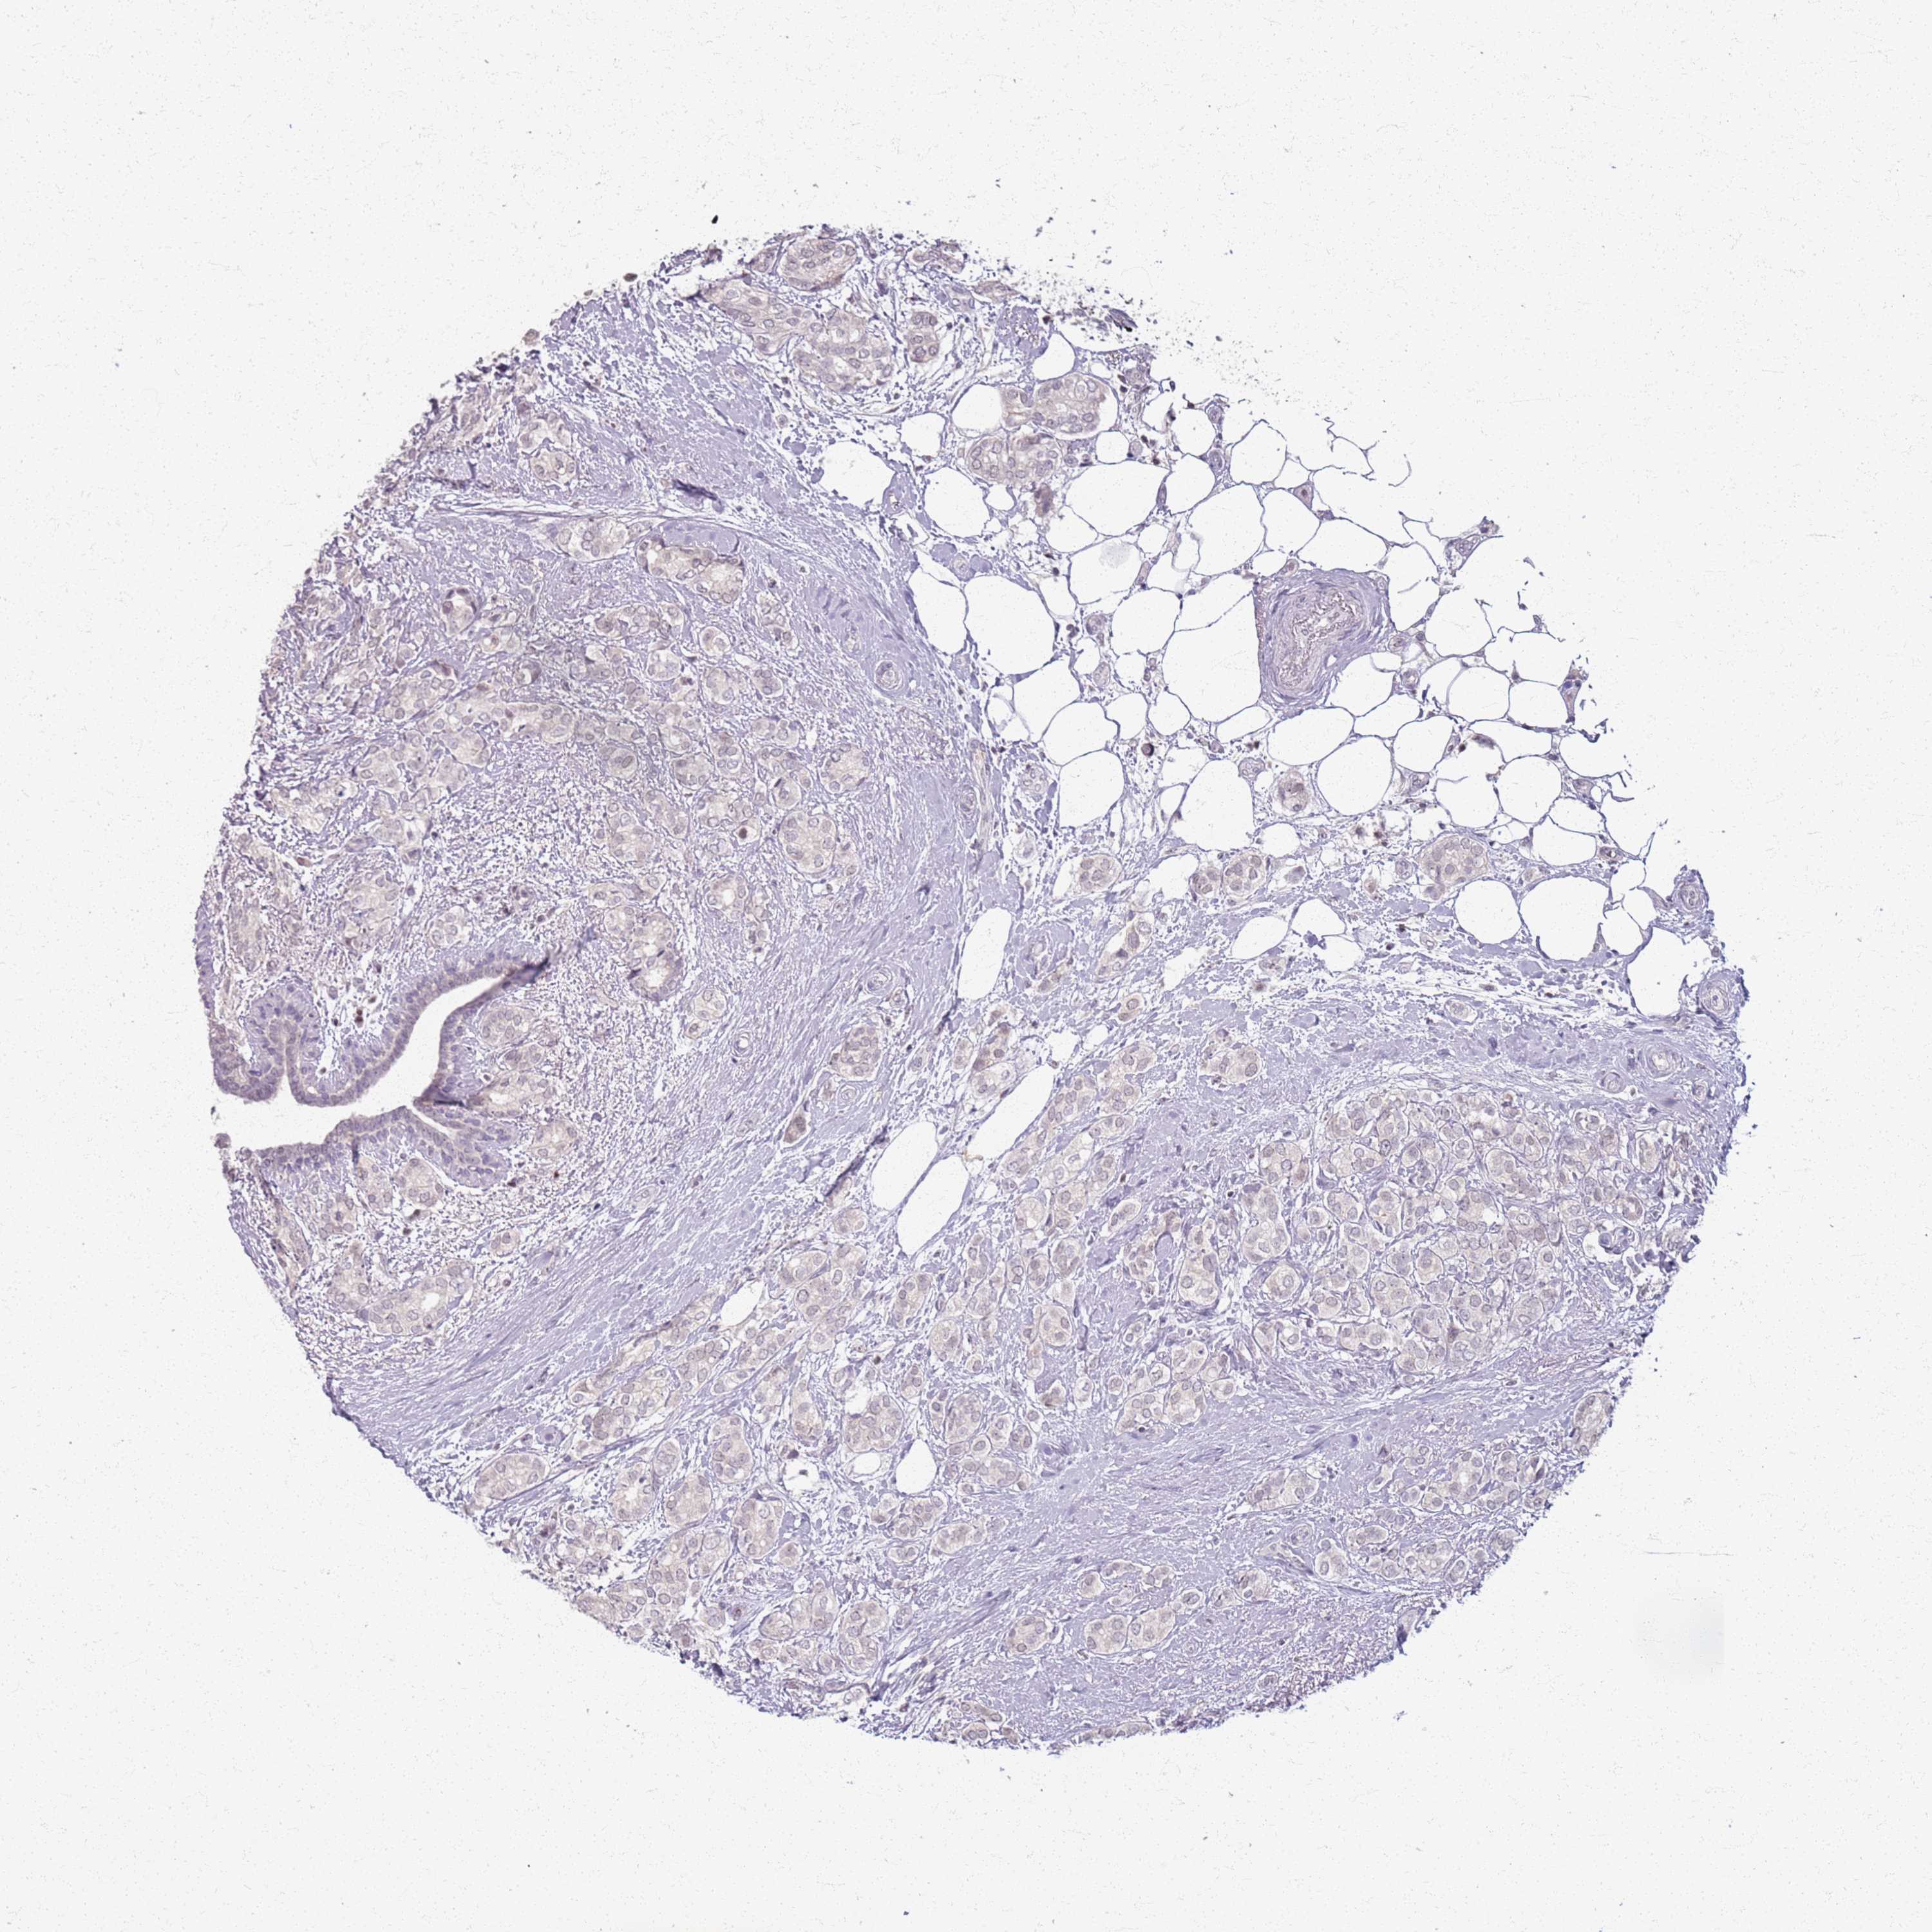

BREAST CANCER - Protein expressioni

A mouse-over function shows sample information and annotation data. Click on an image to view it in a full screen mode. Samples can be filtered based on level of antibody staining by selecting one or several of the following categories: high, medium, low and not detected. The assay and annotation is described here.

Note that samples used for immunohistochemistry by the Human Protein Atlas do not correspond to samples in the TCGA dataset.

Antibody stainingi

Antibody staining in the annotated cell types in the current human tissue is reported as not detected, low, medium, or high, based on conventional immunohistochemistry profiling in selected tissues. This score is based on the combination of the staining intensity and fraction of stained cells.

Each image is clickable and will lead to virtual microscopy that enables deeper exploration of all samples and also displays staining intensity scores, fraction scores and subcellular localization as well as patient and tissue information for each sample.

Antibody HPA044613

Staining

High

Medium

Low

Not detected

Intensity

Strong

Moderate

Weak

Negative

Quantity

>75%

75%-25%

<25%

None

Location

Nuclear

Cytoplasmic/membranous

Cytoplasmic/membranous,nuclear

Duct carcinoma

Lobular carcinoma